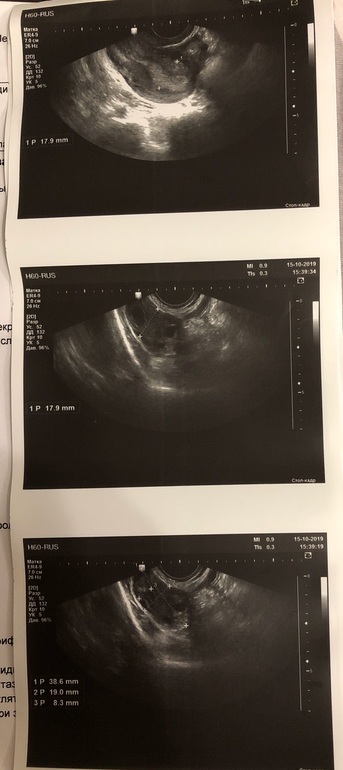

Врач не смогла сказать есть желтое тело или нет.